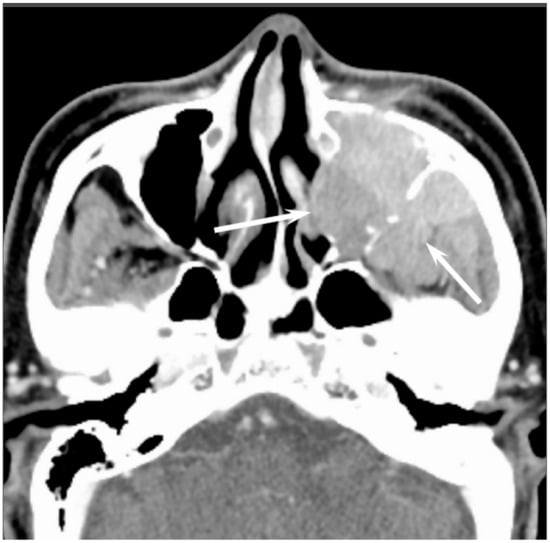

On CT, sinonasal lymphomas frequently show both infiltrative or permeative bony invasion and exhibit varying degrees of regional bony destruction [12]. NHLs with permeative-type tumor invasion typically cross the sinus wall and exhibit remnants of sinus wall as a linear structure within the tumor (Figure 5) [24]. In contrast, bony resorption or remodeling caused by the lymphoma may also be accompanied by bone sclerosis [25]. NHLs usually show isointensity on T1WI and slightly hyperintensity on T2WI [11]. Although the signal intensity of NHLs is nonspecific, the ADC measurement helps differentiate these tumors from other malignancies. In the maxillary sinus, the ADC values of NHL (0.61 × 10−3 mm2/s) were shown to be lower than those of SCCs (0.95 × 10−3 mm2/s), which reflects the greater cellularity of NHLs [12]. Although NHLs usually appear as a homogeneously enhanced mass, necrotic areas within the tumor are occasionally observed in NK/T-cell lymphoma [26,27].

Figure 5. Diffuse large B-cell lymphoma of the left maxillary sinus. Contrast-enhanced CT image showing a homogeneously enhanced lesion accompanied by remaining sinus walls as a linear structure within the tumor (arrows).